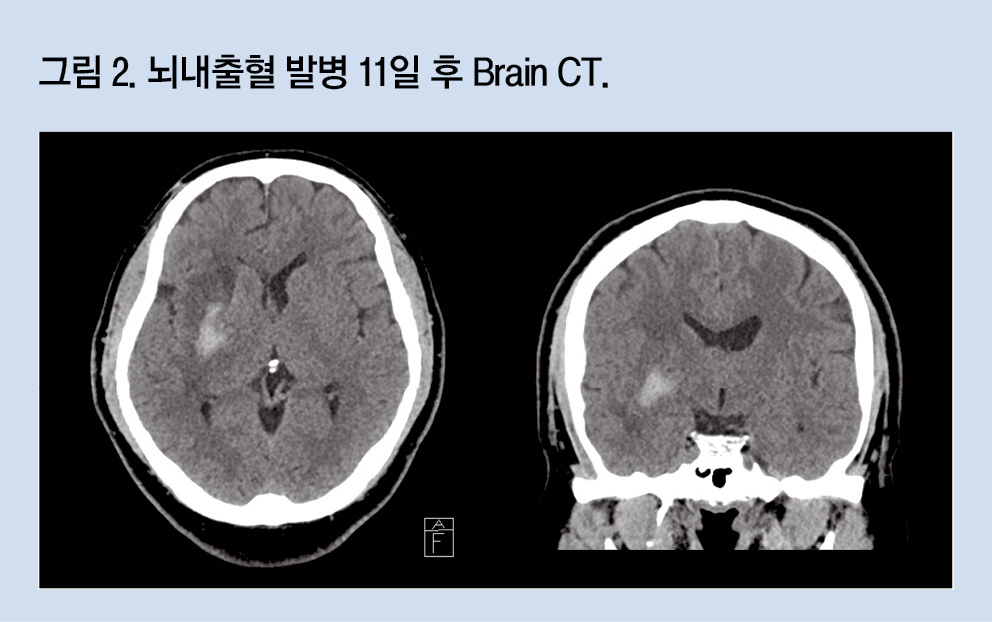

그런데 첫 brain CT 검사를 시행한 날짜를 보니 불과 내원 16일 전이었다. 내원 9일 전 시행한 두 번째 brain CT상 혈종이 약간 감소하기는 하였으나 상당량이 남아있었고, 혈종 주위 부종이 계속 관찰되는 상태였다(그림 2).